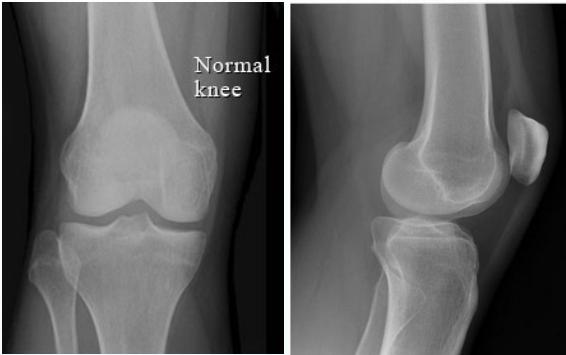

Basic Views:

- AP (Anterior-Posterior)

- Lateral

Additional Views:

- AP standing

- Skyline (patellar view)